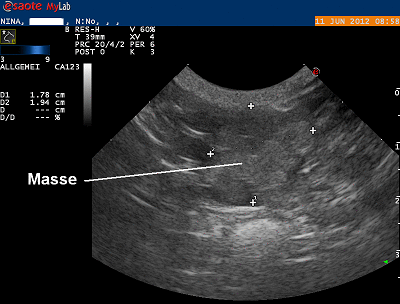

Die Bauchhöhle wird mittels Ultraschall genauer untersucht. Der Knoten erweist sich als unregelmässig begrenzt und von homogener Echotextur. Es ist nicht mit Sicherheit zu klären, ob es sich um einen vergrösserten Lymphknoten oder möglicherweise eine Masse in einer Darmwand handelt. Mit einer feinen Kanüle wird eine Probe zur zytologischen Untersuchung entnommen. Das Pathologielabor diagnostiziert in der Zellprobe einen bösartigen Tumor, welcher aber nicht genauer definiert werden kann.